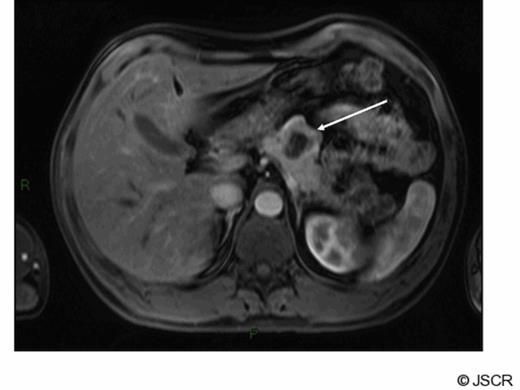

A 42 year old man presented with a history of flushing and sweats and was found on investigation to have a lesion associated with the body of his pancreas. His gut hormone profile was normal and urinary 5-hydroxy indole acetic acid levels were similarly within the normal range. He underwent biopsy of the lesion via endoscopic ultrasound which confirmed the presence of a neuroendocrine tumour of carcinoid subtype. He underwent a spleen preserving distal pancreatectomy for a carcinoid tumour situated in the midbody of the pancreas (fig1).

Arterial phase gadolinium enhanced MRI demonstrating primary tumour (arrow)